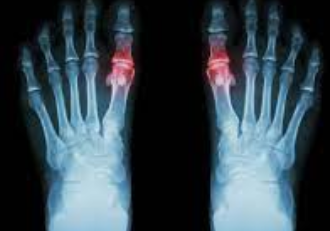

3. 염증 및 발적: 영향을 받은 관절이 부어오르고, 압통이 생기고, 따뜻해지고, 붉어집니다.

4. 운동 범위 제한: 통풍이 진행됨에 따라 관절을 정상적으로 움직이지 못할 수 있습니다.

4. 만성 통풍: 이것은 통풍의 가장 파괴적인 단계이며 치료하지 않고 방치할 경우 발생합니다. 이 단계에서 지속적인 통증과 영구적인 관절 손상이 발생할 수 있습니다.

통풍이 의심되는 경우 의료 도움을 받으십시오. 의사는 요산 결정의 존재를 확인하기 위해 관절액 검사를 사용하거나 혈액 내 요산 수치를 측정하기 위해 혈액 검사를 실시할 것입니다. 그러나 혈액 검사 결과는 오해의 소지가 있습니다. 통풍이 없어도 요산 수치가 높을 수 있고 그 반대도 가능합니다.